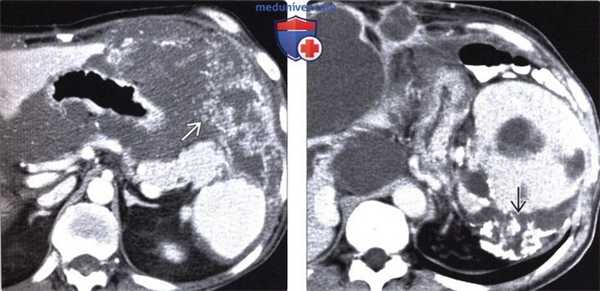

(Слева) На аксиальной КТ с контрастом у пациента с псевдомиксомой брюшины выявлено диффузное поражение брюшины с наличием гиподенсных студенистых образований, распространяющихся в сальниковую сумку и окружающих желудок, а также с более выраженной мягкотканной узловой инфильтрацией с латеральной стороны.

(Справа) На аксиальной КТ с контрастным усилением у пациента с наличием вторичных кистозных очагов (псевдомиксома брюшины), визуализируются вторичные опухолевые очаги содержащие кальцинаты, расположенные возле селезенки. Кальцинаты, чаще всего извитой формы, располагающиеся по периферии очагов, не являются типичным признаком вторичных поражений брюшины при псевдомиксоме.